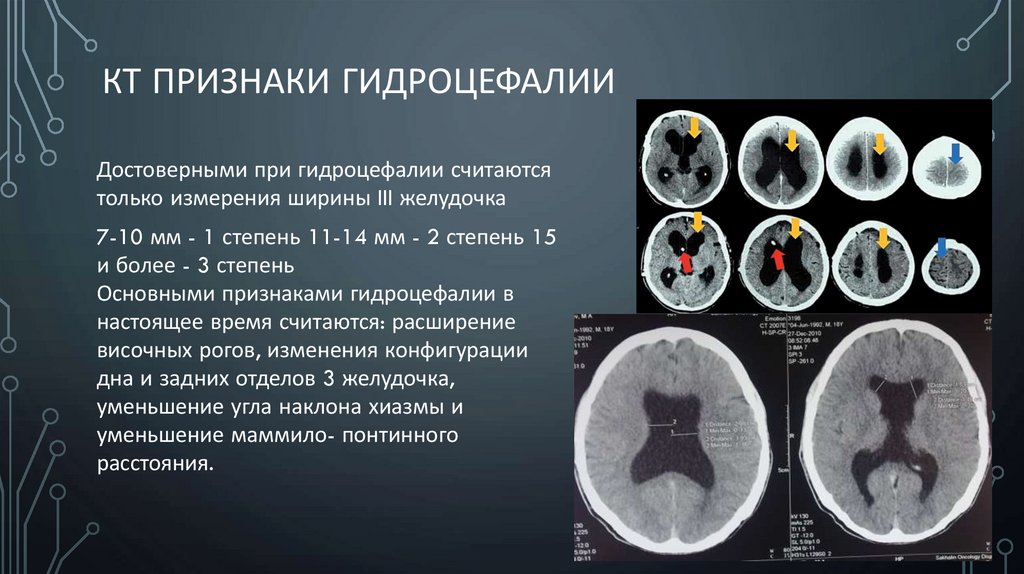

Компьютерная томография в неврологии презентация - 86 фото